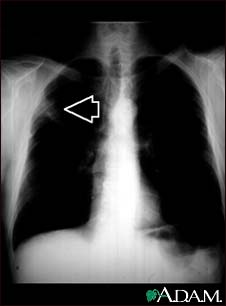

Lung mass, right upper lung - chest X-ray

This picture is a chest x-ray of a person with a lung mass. This is a front view, where the lungs are the two dark areas and the heart and other structures are visible in the middle of the chest. The x-ray shows a mass in the right upper lung, indicated with the arrow (seen on the left side of the picture).